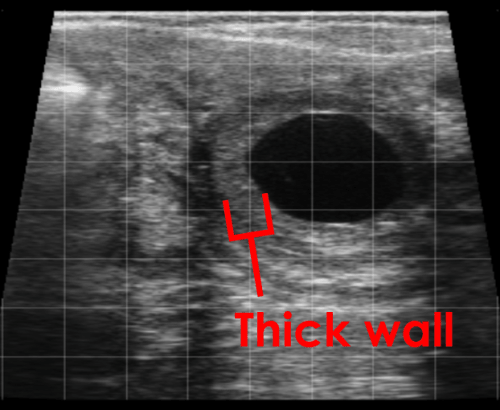

Ovarian Cysts

This image shows a luteal cyst with a central fluid filled area of 25mm. Note the thicker wall of the cyst containing luteal tissue.